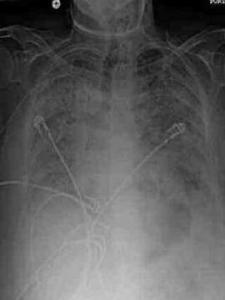

6.影像学检查

绝大部分患者在起病早期即有胸部X线检查异常,多呈斑片状或网状改变。起病初期常呈单灶病变,短期内病灶迅速增多,常累及双肺或单肺多叶。部分患者进展迅速,呈大片状阴影。双肺周边区域累及较为常见。对于胸片无病变而临床又怀疑为本病的患者,1~2天内要复查胸部X线检查。胸部CT检查以玻璃样改变最多见。肺部阴影吸收、消散较慢;阴影改变与临床症状体征有时可不一致。